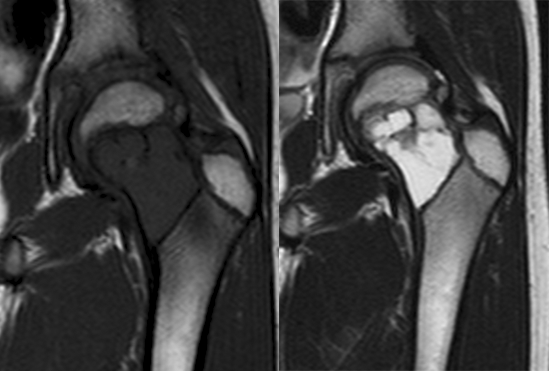

瘤软骨

瘤软骨为肿瘤细胞产生的软骨基质,多来源于软骨类肿瘤,或内有化生瘤软骨成分的其他肿瘤如成软骨型骨肉瘤。瘤软骨为软组织密度,未钙化时,主要通过 MRI 检查显示。由于瘤软骨多由富含水分及粘多糖的透明软骨构成,故 T1WI 呈偏低信号,T2WI 或 PDWI 呈明显高信号,被低信号的纤维间隔分开呈分叶状(图 24、图 25a-b),增强扫描多呈不均匀分隔状强化(图 25c),主要是纤维间隔强化,瘤软骨强化不明显之故。

图 24.瘤软骨:内生软骨瘤

图 25.瘤软骨:内生软骨瘤